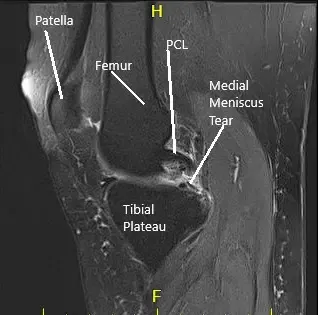

MRI of the right knee suggested medial meniscus tear and patellofemoral arthritis of the right knee.